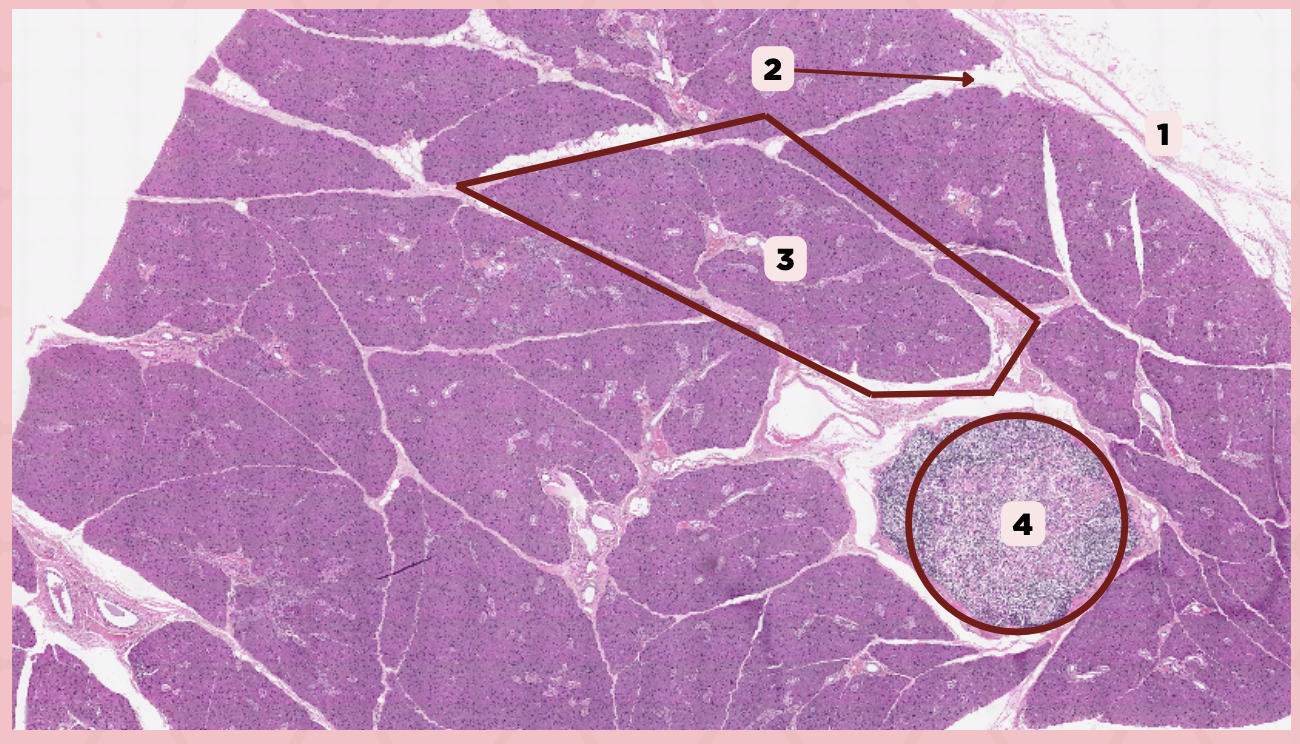

Parotid

Identify the specimen.

Capsule

Identify the structure labeled as 1.

Septa

Identify the structure labeled as 2.

Lobule

Identify the structure labeled as 3.

Lymph Node

Identify the structure labeled as 4.